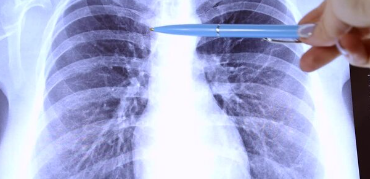

3. 폐결핵 진단: 결핵균 검사, 흉부 X-ray 검사, CT 검사

폐결핵 진단은 다음과 같은 검사를 통해 이루어집니다.

- 결핵균 검사: 가래, 객담, 위액 등에서 결핵균을 검출하는 검사입니다. 결핵균 검사는 폐결핵 진단에 가장 중요한 검사입니다.

- 흉부 X-ray 검사: 폐결핵 병변을 확인하고 폐결핵의 진행 정도를 평가하는 데 사용됩니다.

- CT 검사: 흉부 X-ray 검사에서 발견되지 않은 작은 병변을 확인하거나 폐결핵의 정확한 위치와 범위를 파악하는 데 사용됩니다.